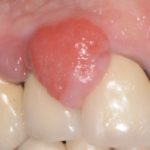

Il root planing invece è quella procedura con la quale viene realizzata una levigatura della superficie radicolare asportando il tartaro residuo e quel cemento che è stato contaminato dal tartaro stesso. Questa fase assume una particolare importanza in quanto la corretta levigatura della radice del dente (accertata con uno strumento, lo specillo ,molto sottile ed appuntito) è l’unico ausilio clinico utile a conoscere se il tartaro sia stato completamente rimosso assieme al cemento necrotico sottostante, con conseguente eliminazione degli stimoli infiammatori sul parodonto circostante.